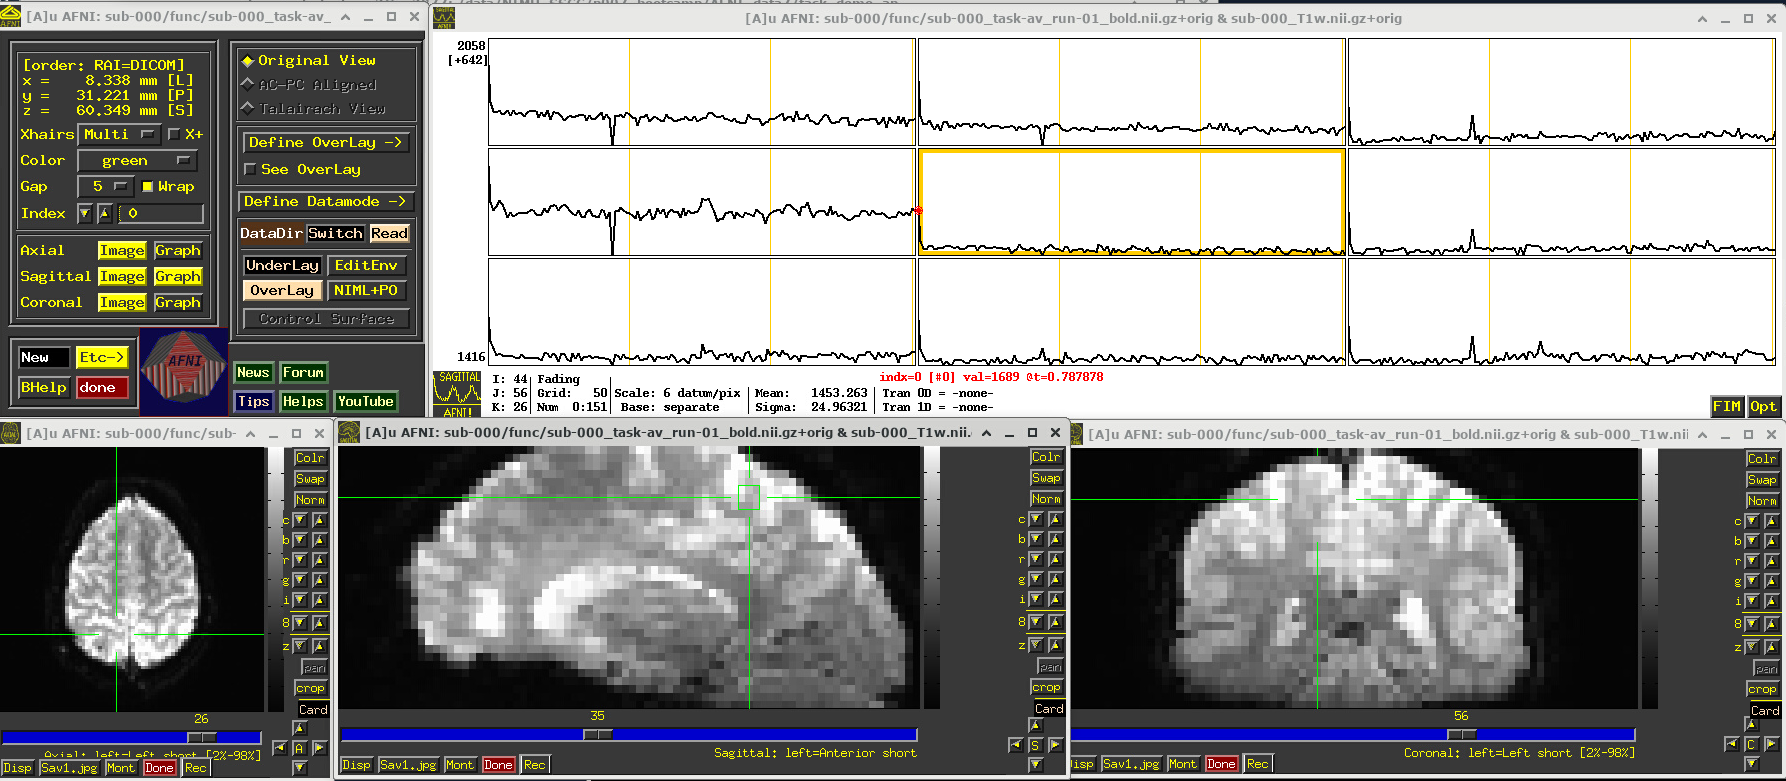

EPI feature: task response

The task performed during this FMRI scan was an audio-visual one. So, let’s check out how things look in the visual cortex. Well, see see some notable patterns, such as at the location (x,y,z) ~ (16, 78, 3.3), as below. While the earlier-noted motion and pre-steady state spikes apparent, we now see some very regular pattern of hills. And indeed, these are signatures of task-related BOLD response for this block design paradigm (we could load the idealized response time series into the graph viewer, too, to help verify this).

Specifically, this paradigm has the start of a block that contains either a blurred or clear visual component every 30s and a duration of 20s, so seeing regular response in the visual cortex is not unexpected. The fact that we see a few time series in this graph montage with the task signature reflects our spatial sampling: the voxel edges are roughly the same diameter as GM cortex. Notice also that the response shapes aren’t perfectly rectangular—the BOLD response is not on/off, but has a ramp up and ramp down—and that notable plus/minus noise bumps are still present.

Later, we will look at performing real processing to get a more detailed description of task responses: quantifying each stimulus class, perhaps comparing them (i.e., evaluating their “contrast”), trying to boost their signal-to-noise ratio while also reducing spikes and other noise features. That is the job of the real processing.

# Display a screenshot of the AFNI GUI with the first EPI run loaded

IPython.display.Image(filename='example_snapshots/img_03_afnigui_epi_r01_taskresp.png')

../_images/df242a56362284883d4e5b72322ff8de8574fb812b73727711a90463314798b7.png